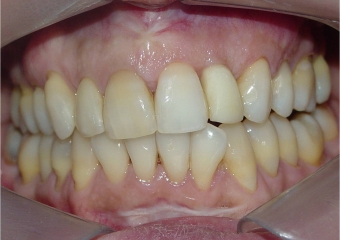

Sorriso final, do caso terminado em Agosto de 2014 - Clínica Cliniface

Sorriso final, do caso terminado em Agosto de 2014